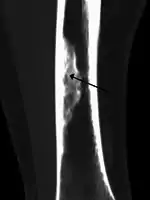

| X-ray of nonossifying fibroma of distal tibia. | |

Diagnosis is by X-ray or MRI, usually when investigating a person for something else.[2] Medical imaging typically shows a well defined radiolucent lesion, with a distinct multilocular appearance, sometimes looking like bubbles.[2] It is usually around 1-2cm in size, but be as large as 7cm.[3] They consist of foci consist of collagen rich connective tissue, fibroblasts, histiocytes and osteoclasts.[2] Usually no treatment is required.[1] Surgical curettage and bone grafting may be required if it is large.[3]

It is usually diagnosed by x-ray or MRI, when investigating another problem.[1] The tumor presents as a well defined radiolucent lesion, with a distinct multilocular appearance, sometimes looking like a "soap bubble".[5] If small and no symptoms, then biopsy is not needed.[1]